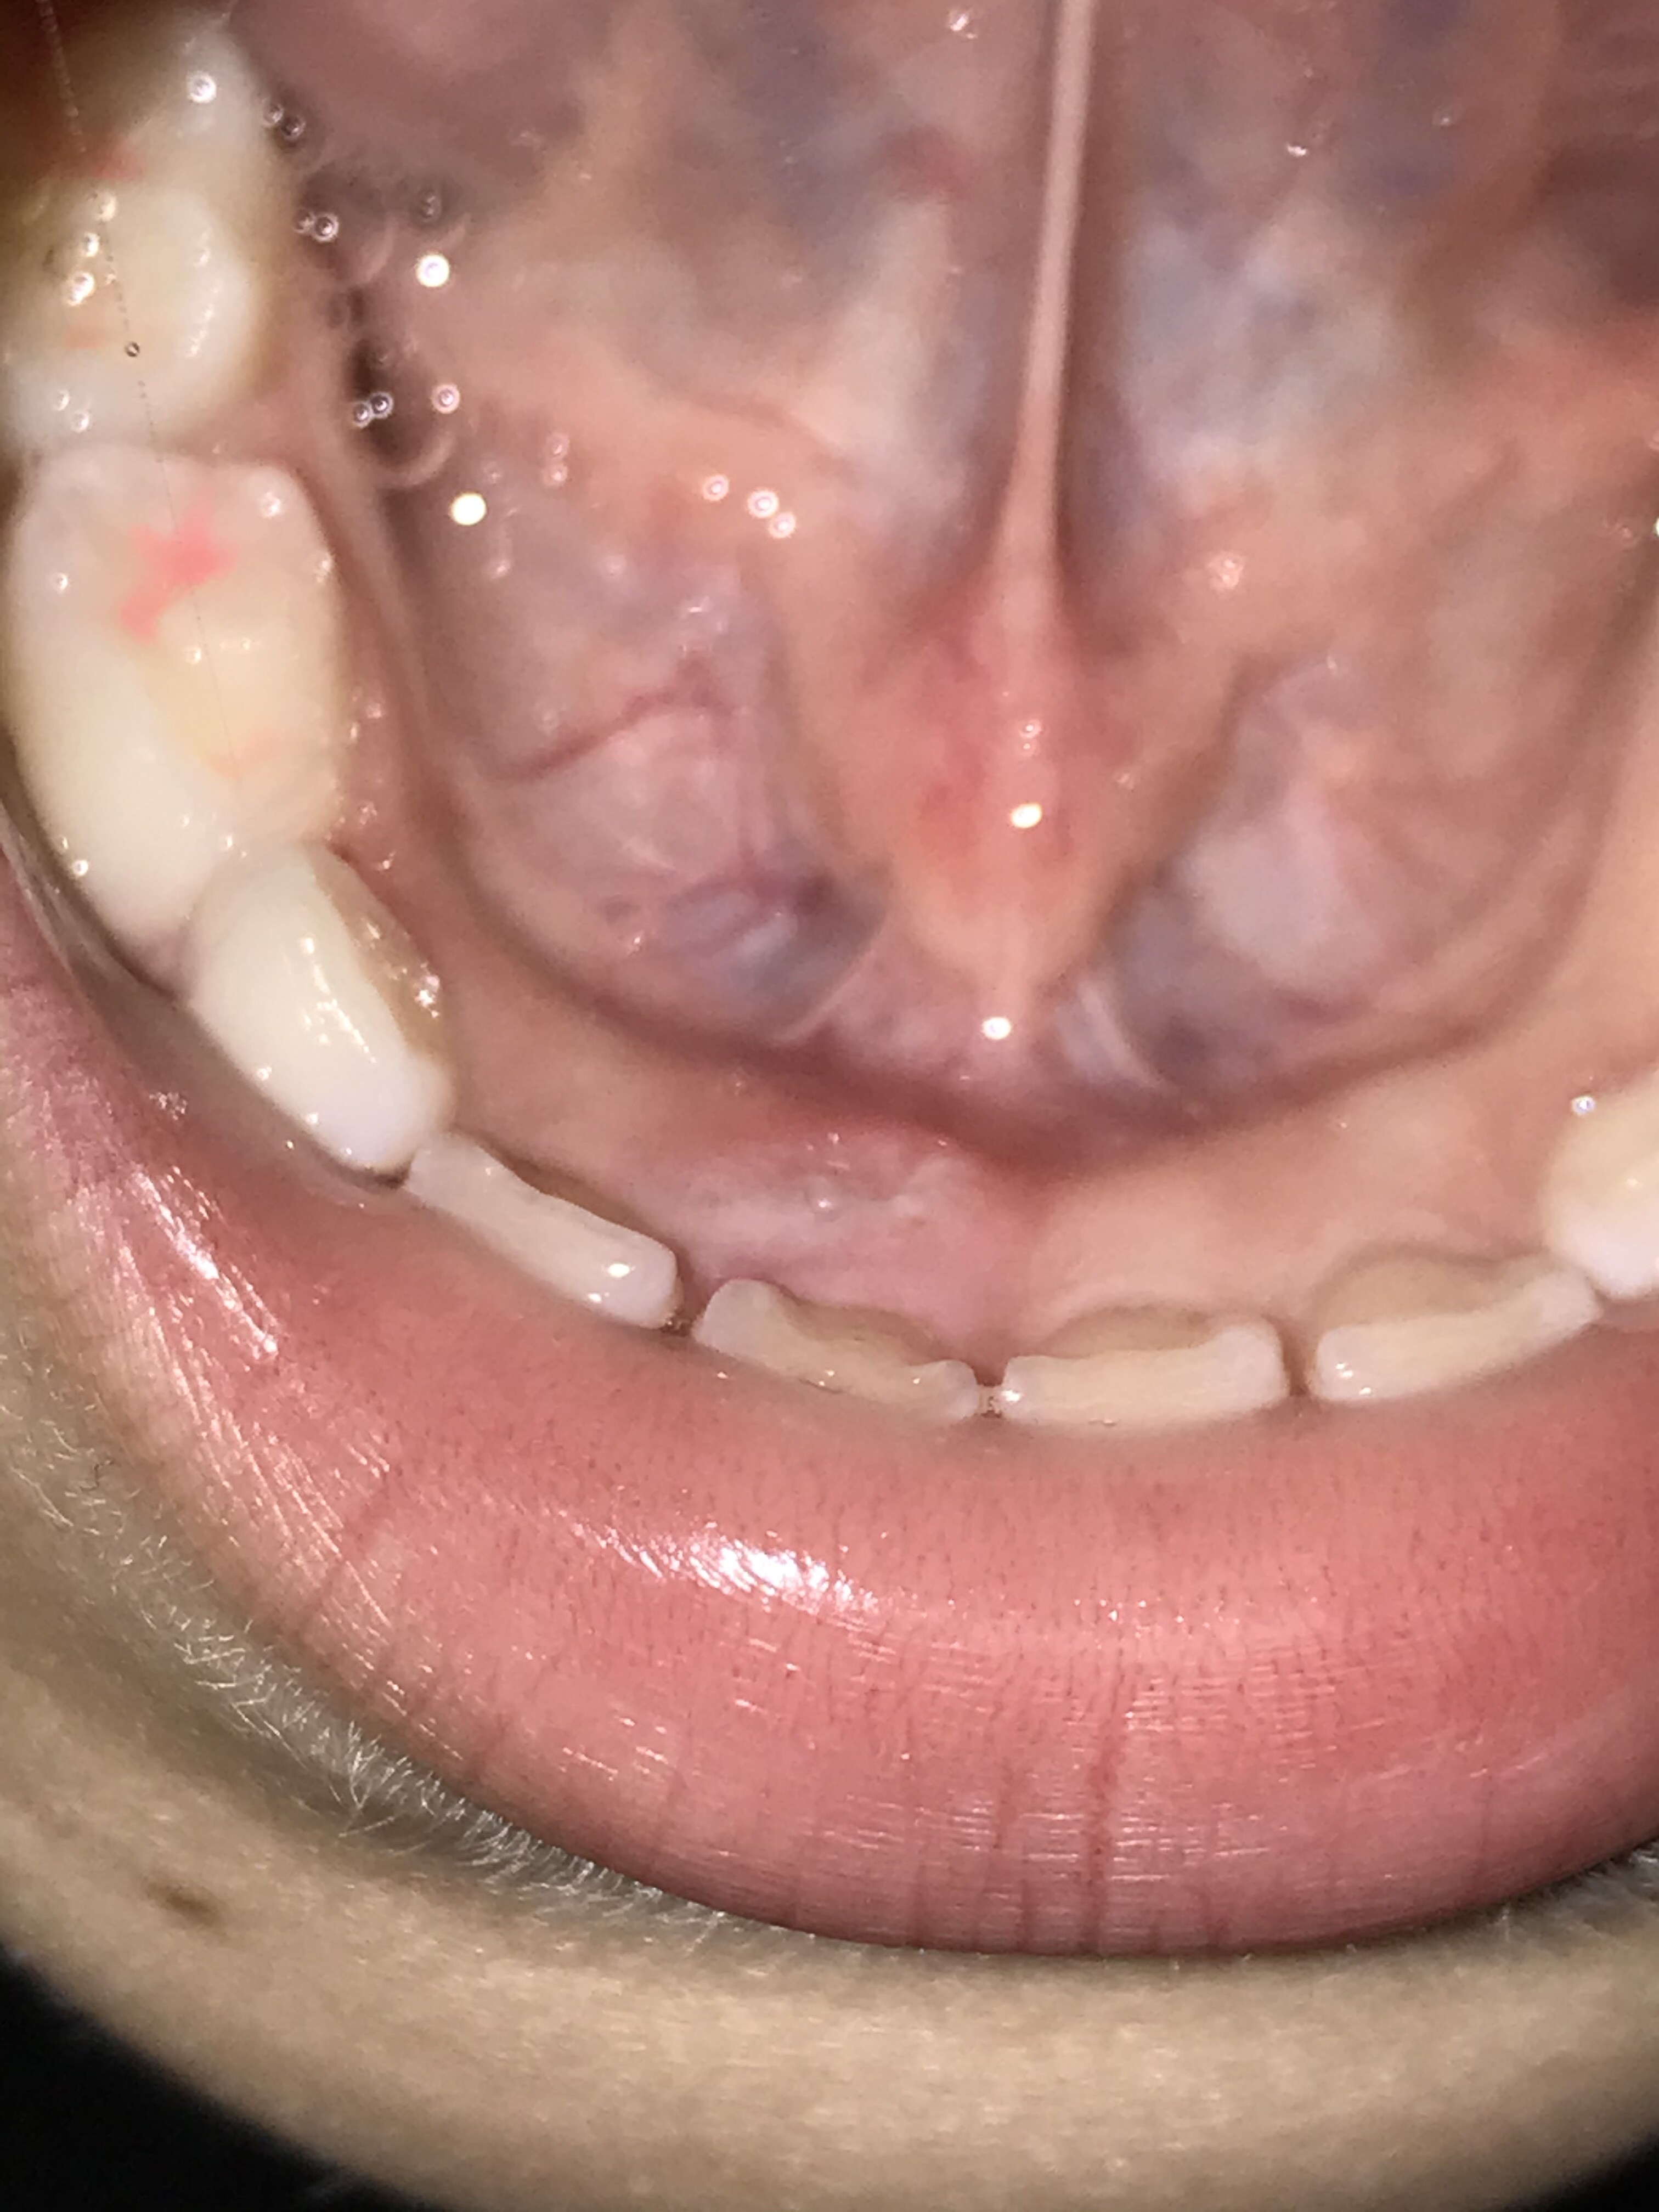

前歯のグラついてる歯の後ろから明らかに永久歯が生えてきてる〜

これってこのままでいいのか分からないから行きつけの歯医者でも見てもらう事にしました

せっかく奇麗な歯並びなのにグチャグチャにならないか心配なの〜